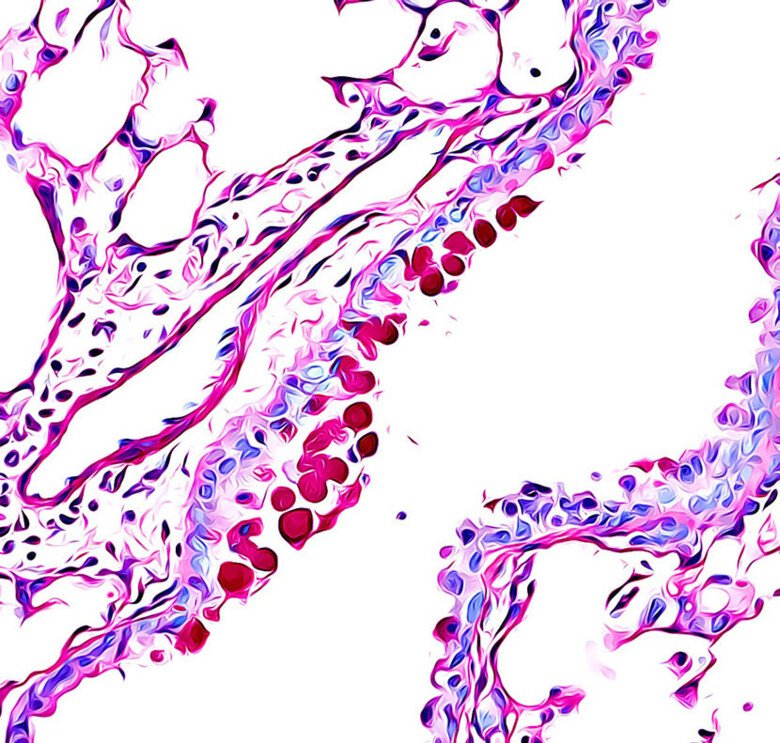

Our group is interested in how T cells develop and differentiate in response to antigens and cytokines. In particular, the group is focused on understanding the role of T cells in allergy and cancer.

T cells recognise peptide/lipid ligands presented in the context of MHC or MHC-like molecules expressed on antigen presenting cells. In particular, the group has a special focus on CD4 T cells, which when activated differentiate into T helper cells with potent cytokine-secreting function. Over the past three decades, several distinct T helper cell subsets have been described including Th1, Th2, Th17, Treg and others and these all exert quite unique immune modulatory effects. My group has many interests, including:

Our group is interested in understanding immune responses to allergens. T helper cells, in particular IL-4, IL-5 and IL-13 producing Th2 cells have a central role in mediating the pathogenesis of asthma. Over the last few years, we have demonstrated that these cells are characterised by the high expression of genes associated with lipid metabolism including PPAR-g, which likely regulates metabolism in Th2 cells and also promotes effector gene expression.

Many other T helper cell subsets are thought to regulate asthma, especially in adults, and we are interested in characterising T helper cells in different phenotypes of asthma and allergy. Right now, we have a focus on performing single cell RNA-Sequencing analyses in different clinical and preclinical contexts, in order to paint a really clear picture of the T helper cell phenotype in different allergies.